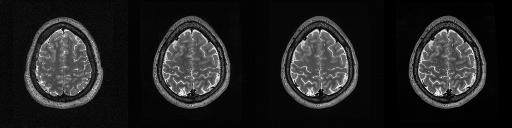

HCP T2w dataset

We utilize images from the publicly available Human Connectome Project (HCP) [51] T2-weighted (T2w) images dataset for the task of compressed sensing, which contains brain images from 47 patients. The HCP dataset includes cross-sectional images of the brain taken at different levels and angles.

Compressed sensing

We train a flow-based model from scratch on 10,000 randomly sampled images, utilizing the ncsnpp architecture [9] with minor adaptations for grayscale images. We employ compression rates , meaning . The measurement operator is given by a subsampled Fourier matrix, whose sign patterns are randomly selected. We evaluate our reconstruction algorithm’s performance on 200 randomly sampled test images.

We present the quantitative and qualitative results of compressed sensing in Tab. 1 and Fig. 4, respectively. As shown in Tab. 1, our method consistently achieves the best performance across varying compression rates . In Fig. 4, our method produces reconstructions that are more faithful to the original images, with fewer artifacts, leading to higher accuracy and clearer details.